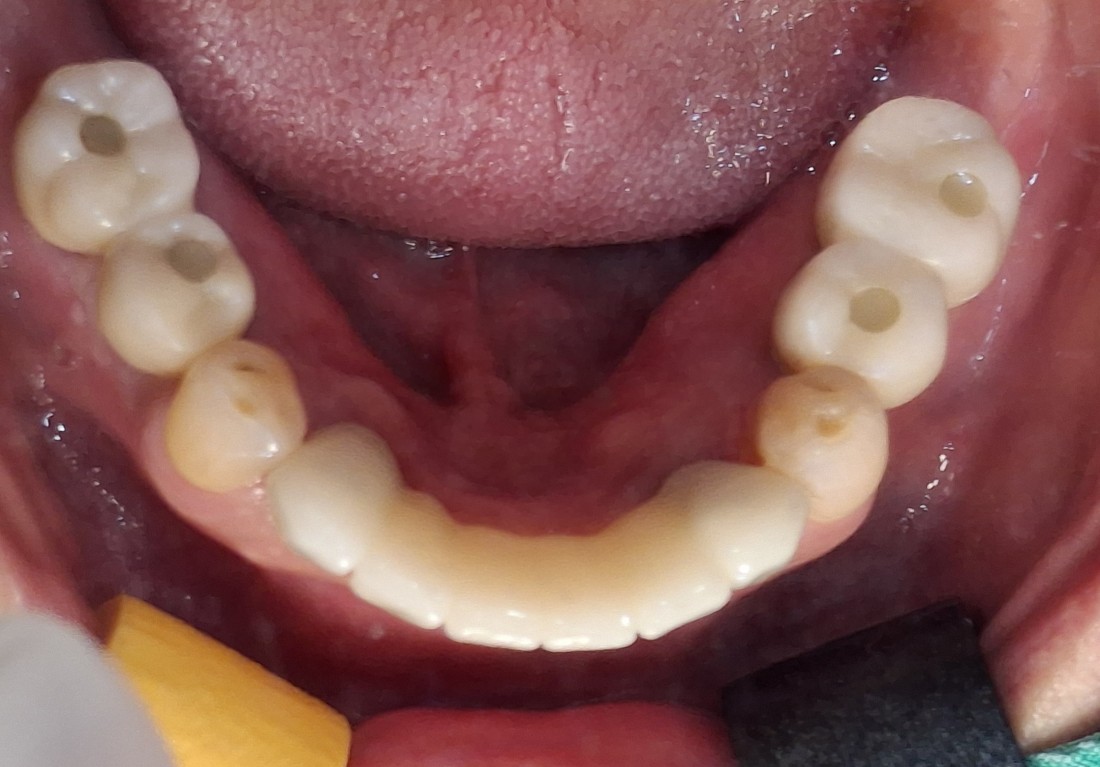

수완동 임플란트 치과는

자체 치아기공소를 운영하고 있습니다.

대표원장인 제가 직접

치아기공소의 보철물 퀄리티를

관리하고 있기 때문에,

무엇보다도

< 예쁘게, 잘 씹어지는 >

수완동 임플란트를 약속드릴 수 있습니다.

잘 관리하면 반영구적으로 사용할 수 있는

임플란트이기 때문에

특히 자연치아보다 더 자연스러운

아름다운 임플란트를 완성하는

수완동 임플란트 치과입니다.

수 백개의 임플란트 전/후 케이스 사진을

홈페이지에 공유하고 있습니다.

전체 임플란트부터

신경쓰이는 앞니 임플란트,

20대 / 30대 임플란트 케이스부터

80대가 넘는 분들의 케이스까지

정말 다양한 모든 케이스를 보유하고 있습니다.

다양한 각도의 임플란트 식립 전/후 사진으로

실력에 자신있는